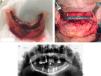

Solamente 6 pacientes tenían fístulas (32%) (fig. 3 a-b, tabla 1).

Hubo 7 pacientes en estadio 1 (37%) (fig. 1 a-b), 8 en estadio 2 (42%) (fig. 2a-b) y 4 en estadio 3 (21%) (fig. 2 c).

Los pacientes en estadio 3 fueron tratados en todos los casos con mandibulectomía segmentaria. Tres de ellos fueron reconstruidos con colgajo microquirúrgico de peroné (fig. 4 a-c), y uno con barra mandibular más cierre directo. Fueron tratados mediante secuestrectomía 7 pacientes, de los cuales 5 tenían estadio 2 y 2 estadio 1. Con desbridamiento local solo fue tratado un paciente que presentaba estadio 1. El tratamiento conservador se aplicó al resto de los pacientes en estadio 1 (4 pacientes) y a 3 pacientes del estadio 2.